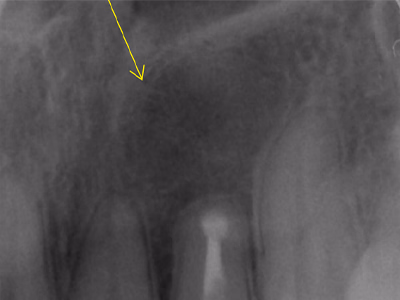

治療前後写真

治療前

治療後

奥歯がしみて痛む(右上第2大臼歯 #27)

治療内容

- ① CT診査で根管形態を把握

- ② マイクロスコープ+ラバーダム下で抜髄(根管清掃)

- ③ 2回目で根管充填・ファイバーコア封鎖

- ④ 3回目:支台歯形成・印象

- ⑤ 4回目:セラミッククラウン装着

抜髄後数日で痛みが消失。

セラミック装着後も正常に咀嚼でき、現在は年1回の定期検診で良好な経過を維持。